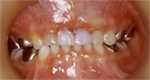

|

治療後 |

穴のあいてしまったむし歯の治療は、おとなと変わりはありません。むし歯の部分を削ってコンポジットレジンというプラスチックや金属で治します。むし歯が大きい場合には金属の冠で治します。歯の中の神経まで進行している場合には、神経をとらなければならず、治療も数回かかります。多くの場合で局所麻酔が必要となるので、お子さんにとってはいやなものです。新たなむし歯ができないように、むし歯予防をしていきましょう。